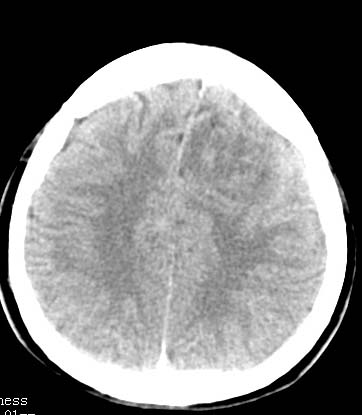

以下是引用clj20在2007-8-29 9:47:00的发言:[br]蛛网膜下腔出血,左侧额叶不均匀密度影,占位效应明显,界限不清。支持:占位性病变,建议增强!

以下是引用xulianj在2007-8-29 20:15:00的发言:[br]蛛网膜下腔出血,左侧额叶不均匀密度影,占位效应明显,界限不清。支持:占位性病变,建议增强!

以下是引用jiangjing在2007-8-29 14:33:00的发言:[br]左侧额叶不均匀密度影[低密度为主,边缘见等密度环环绕]占位效应明显,界限不清。支持:占位性病变,建议增强! [br][br]